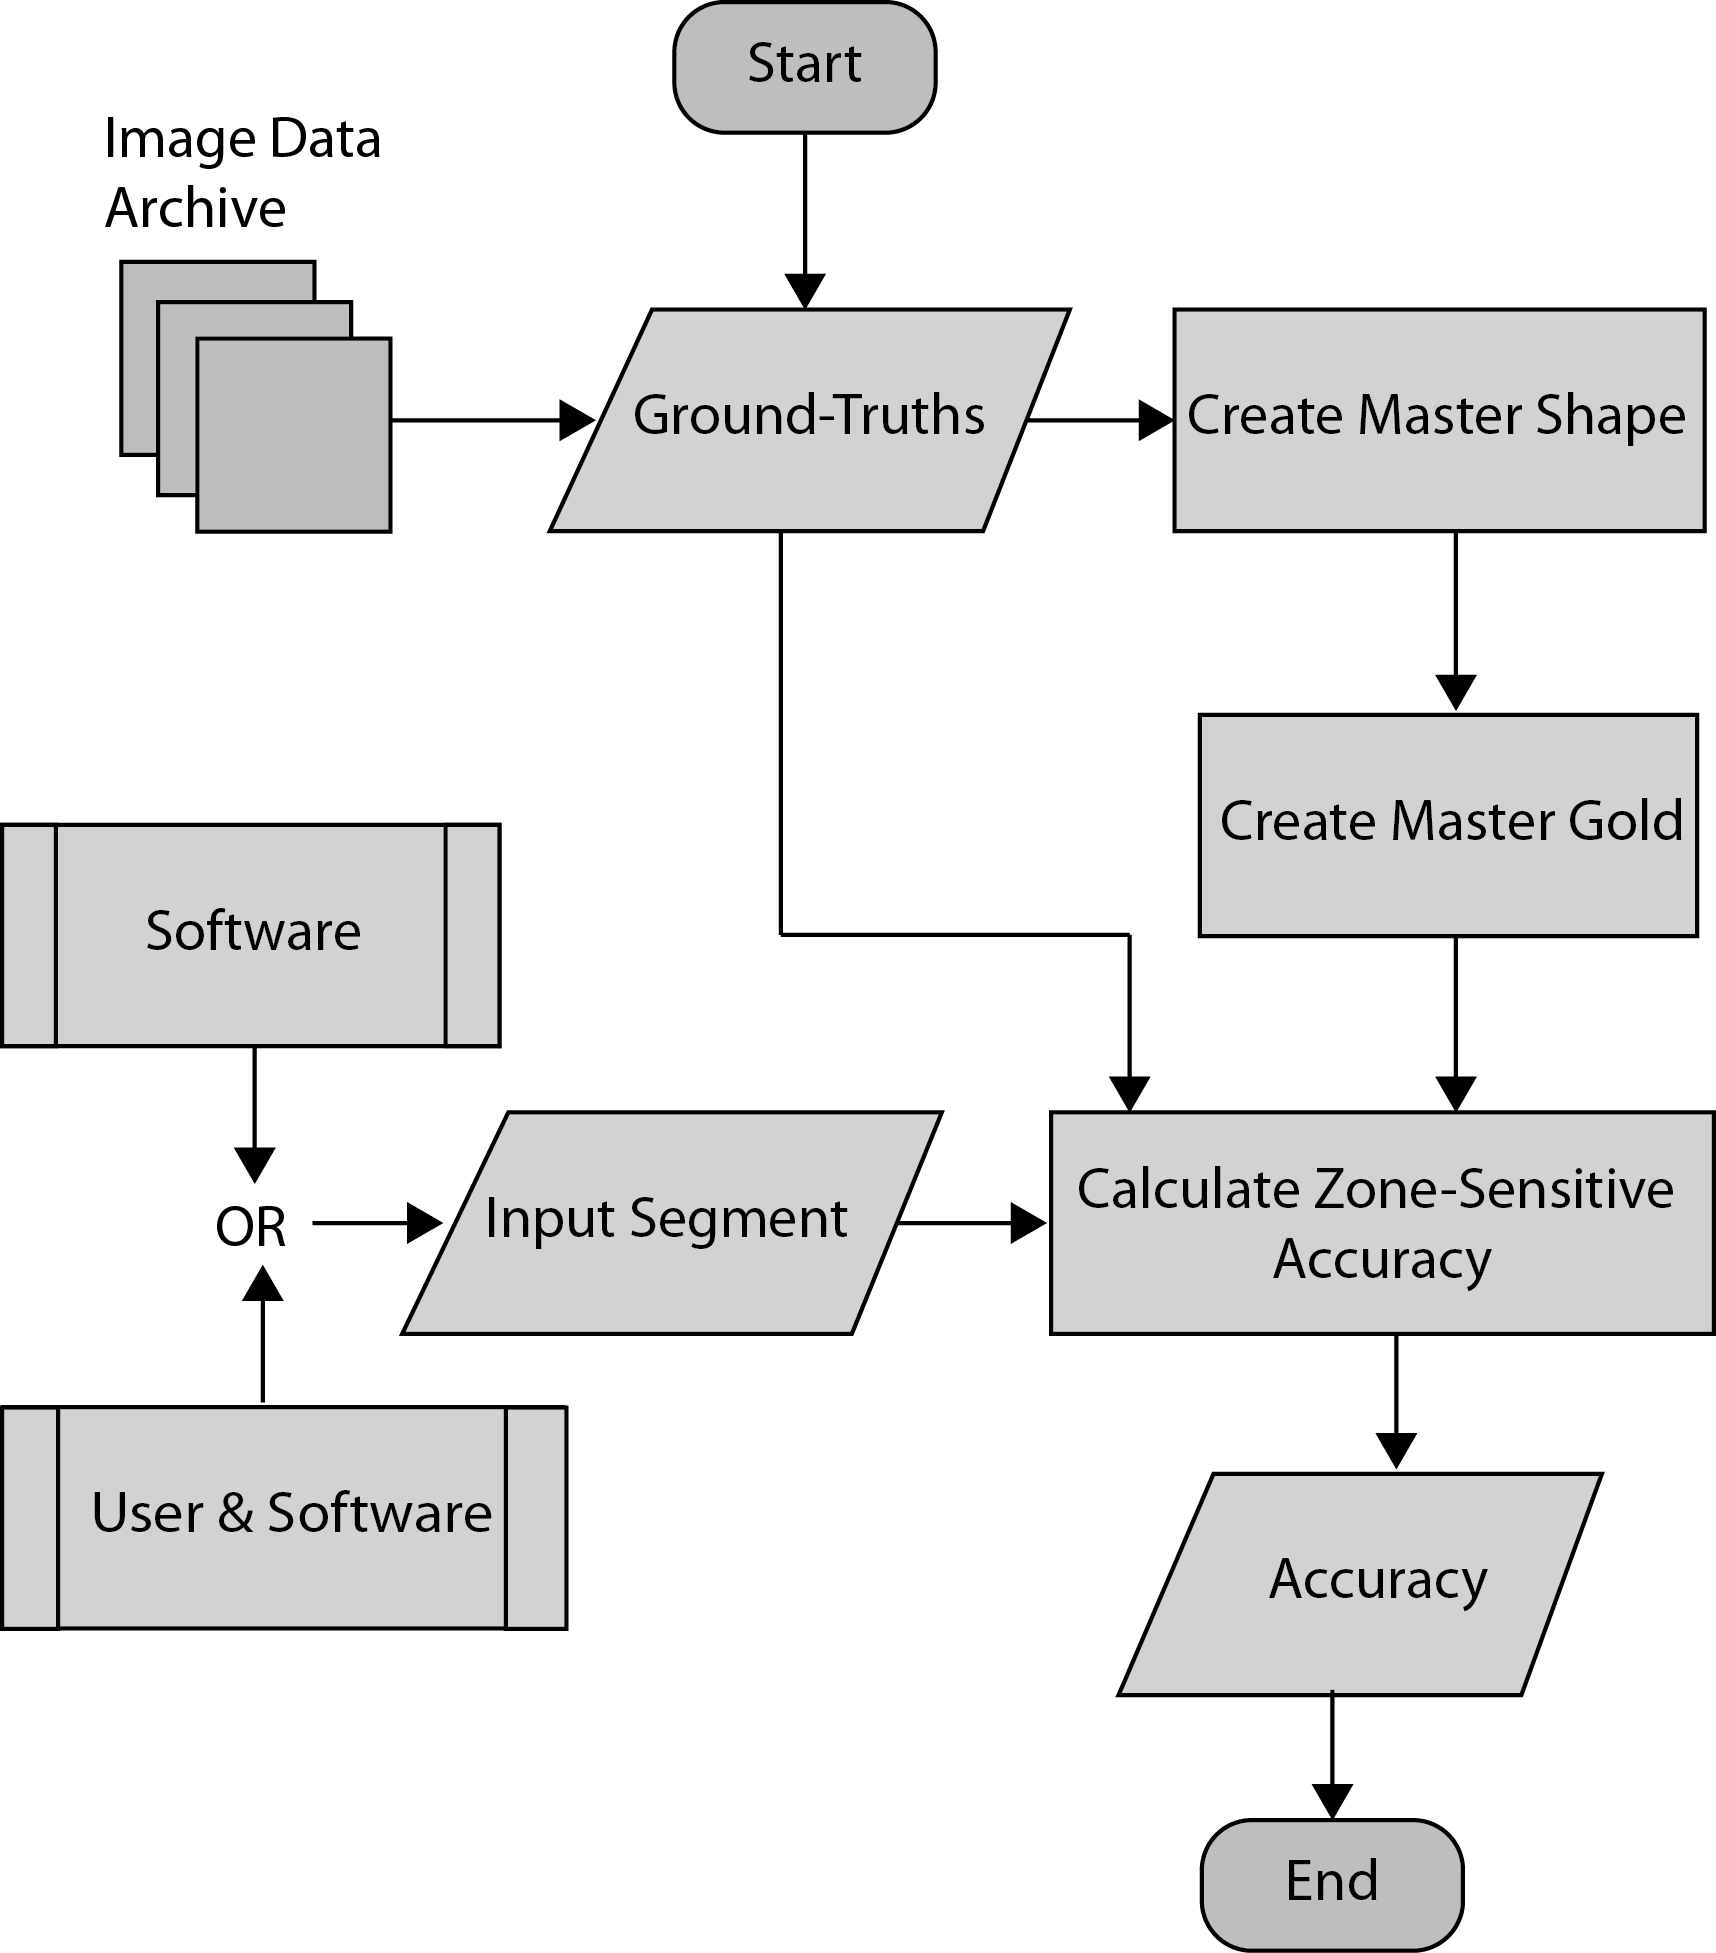

The zones have to be highlighted in a “master shape”, a general or statistical shape that represents the expected shape appearance of the organ or tumor. Of course, such an approach can only address the cases with more or less regular shapes, e.g., organs and compact masses such as cysts and nodules. As well, it would need to be done only once in order to not create additional work for the clinical experts. A master shape with zones inside would then constitute a “master gold”. Every time that we have a segment and corresponding ground-truth, we can map the zones from the master gold to the current ground-truth and subsequently to the segment. This finally enables us to perform zone-sensitive accuracy measurements provided we also have some zone-sensitive accuracy measures (if we extend existing ones to become aware of zonal anatomy within the segment) to capture the compound accuracy. The outline of this idea is illustrated in Figure 1.